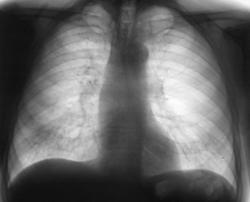

После расшифровки (2007 г.) цифровых флюорограмм пациент "взят на контроль". Заподозрено наличие очагов средней интенсивности справа на верхушке и некоторое субплевральное снижение прозрачности легочной ткани (помечено красными стрелками). Произведено дообследование, сомнения не рассеялись, а лишь укрепились. Пациенту рекомендована консультация фтизиатра. Фтизиатр направлен пациента в специализированное учреждение.

После расшифровки (2008 г.) цифровых флюорограмм пациент "взят на контроль". Взят на контроль, именно с учетом "сомнительной плотности" очагов. Однако, от дообследования пациент отказался, мотивируя тем, что он был "там-то и там-то", где "его обследовали и ничего страшного не выявлено".

2009 г. Пациент направляется на диагностическую флюорографию терапевтом с диагнозом "Правостороняя пневмония". Произведены цифровые флюорограммы в прямой и правой боковой проекциях.

Через 2 недели после проведенной противовоспалительной терапии пациент чувствует себя хорошо, "стоит" вопрос о выписке из стационара. Проведено контрольное рентгенологическое исследование в стандартных проекциях.